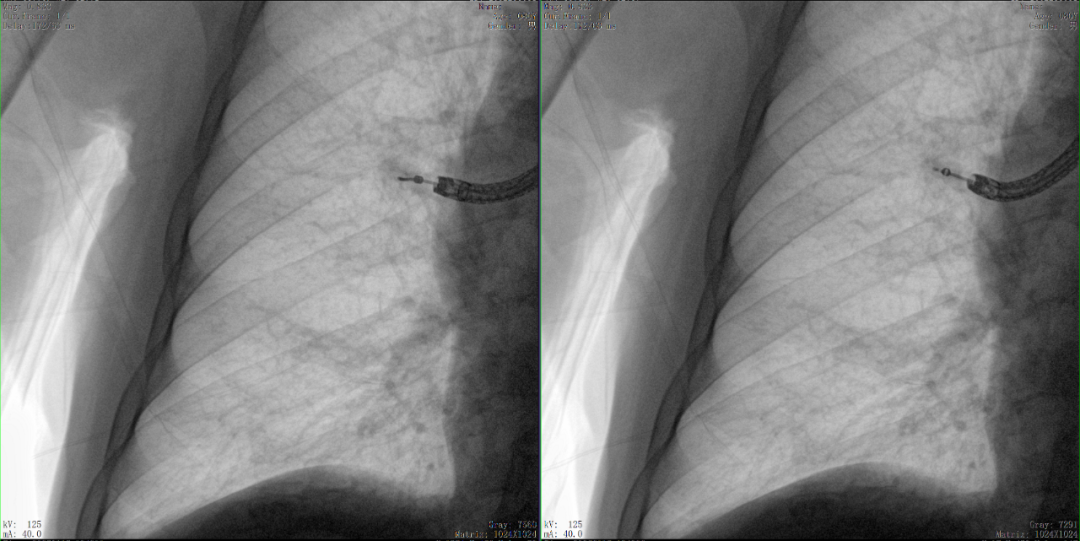

病例2 踝关节骨折复位(31岁)

在踝关节骨折复位手术中,用三维C可以更好地观察骨折部位的复位情况:

正侧位影像观察胫腓联合复位良好

从三维影像看,复位欠佳,贴合度不够